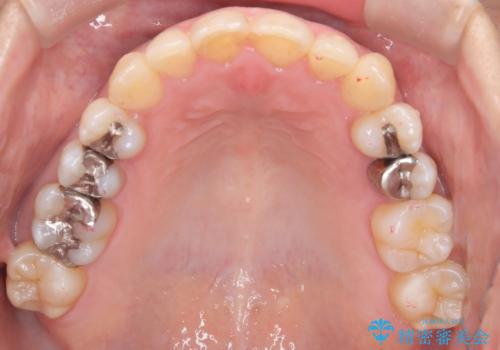

【インビザライン】重度叢生をなおしたい

- 全体的に歯並びをなおしたいことを主訴に来院されました。

上顎前歯が舌側傾斜していたため少し拡大を行いながら非抜歯で治療を行っています。

マウスピースをしっかり使用していただいたので、きれいな歯並びになりました。